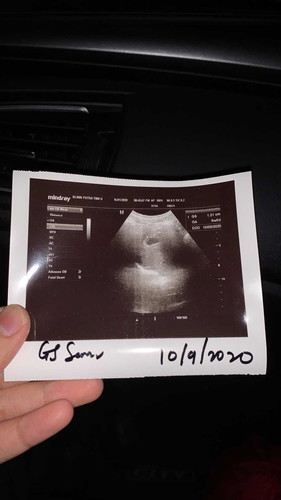

Tiada janin and jantung. 6week

Salam semua saya baru scan tadi. Tapi sebelum ni scan xde kantung tp ni dah ada kantung cuma tak ada janin n jantung lagi. Doc bg ubat kuat rahim and 2minggu lagi doc suruh datang. Normal ye kalau scan macam ni tak de janin n jantung. Saya bukan apa risau anak first.

Đọc thêmsama mcm saya sis... baru je scan tdi..saya scan ikut bawah sbb ade kes extopic 5thn lps... ikutkn skg dh 6w3d...tapi nmpk kantung jew.. blm nmpk janin n jantung lagi... alhamdulillah, kandungan kali ni dalam rahim & doc suh repeat lgi 2 minggu.. blh saya tau ukuran kantung sis brape cm?